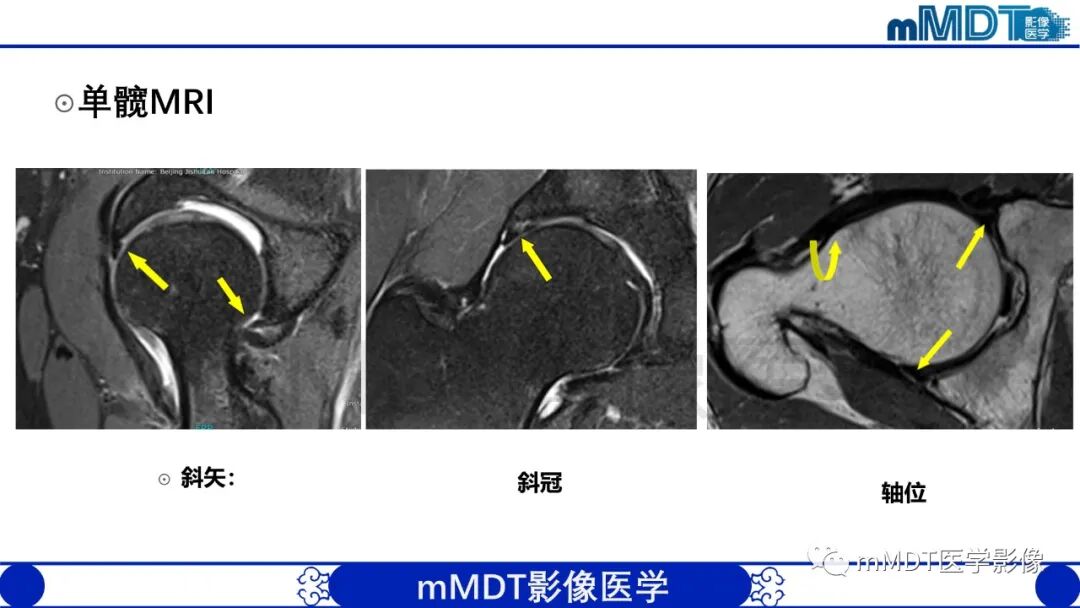

MRI:直接显示髋臼盂和关节软骨损伤

MRI显示主要征象:盂唇内高信号、盂唇形态异常、软骨移行区剥脱或分层、连续性中断;次要征象:滑膜疝;盂唇旁囊肿。提示髋臼盂唇撕裂或损伤。